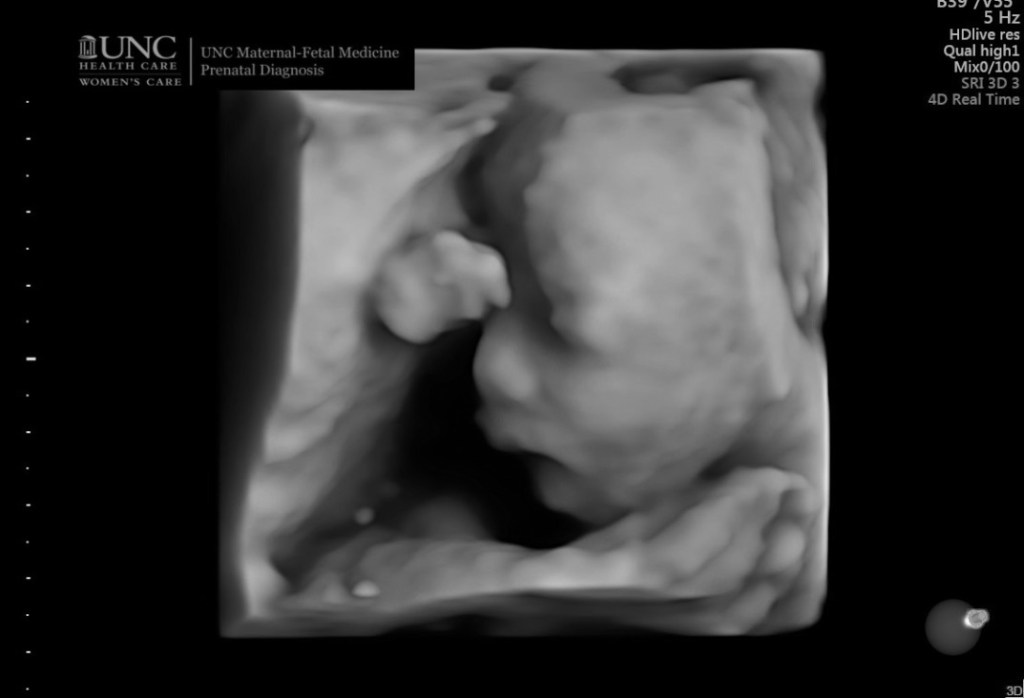

These were the scriptures I had in my heart when Daniel and I were begging for Ginny’s life. In that dark ultrasound room, the technician said that she was having trouble finding the heartbeat. I started panicking. Then I remembered that my God works miracles. The technician left to get a doctor, and Daniel and I prayed harder than we’ve ever prayed before. In Jesus Name Ginny Will Be Born Alive!! We are asking for a MIRACLE! Please please let Ginny grow up. Give her life! Please FATHER!!

The doctor arrived, “I’m so sorry.” We had our answer. I was shocked.